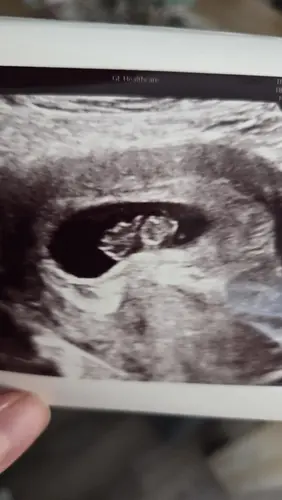

Afgelopen maandag ongeveer 8 weken ❤️ van kruin tot stuit 1,6cm

Wat een prachtige echo!!!!🩷